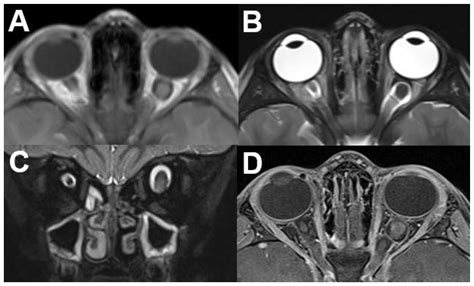

• Magnetic Resonance Imaging (MRI) scans: Offer high-resolution images of the soft tissues, muscles, and nerves within the orbit.